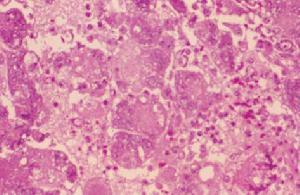

喉头水肿为喉部松弛处的粘膜下有组织液浸润。其病因有感染性和非感染性两大类。感染性喉水肿可因急性喉炎、急性会厌炎、急性喉软骨膜炎、喉部脓肿、喉结核、喉梅毒等以及咽部或颈部的急性化脓性炎症所引起;非感染性喉水肿可因心脏病、肾炎、肝硬化、甲状腺功能低下,过敏性或遗传性如注射青霉素,口服碘化钾、阿斯匹林等药物以及过敏体质者食用致敏食物如鱼、虾、蟹等原因。

症状:喉痛、声嘶、喉喘鸣和呼吸困难,并可伴发热恶寒,咽喉疼痛,喉镜下可见粘膜呈深红色水肿、表面发亮,喘鸣,声嘶,呼吸困难,甚则窒息,喉镜下可见喉粘膜弥漫性水肿,苍白